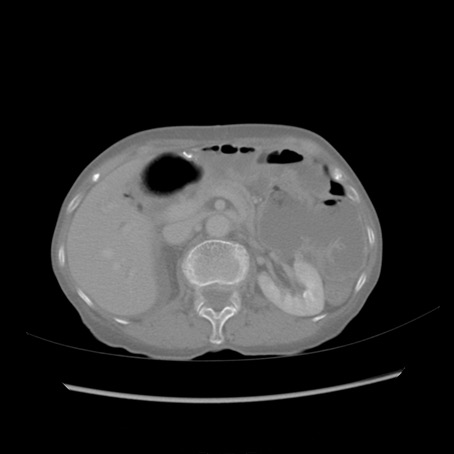

症例25(横断像)

【症例】80歳代女性

【主訴】胸のつかえ感

【現病歴】約9時間前に食後から胸のつかえた感じあり、嘔吐あり、来院。

【既往歴】胃癌(全摘)、胆摘、虫垂炎

【身体所見】心窩部に圧痛あり、反跳痛なし。

【データ】WBC 5700、CRP 0.05